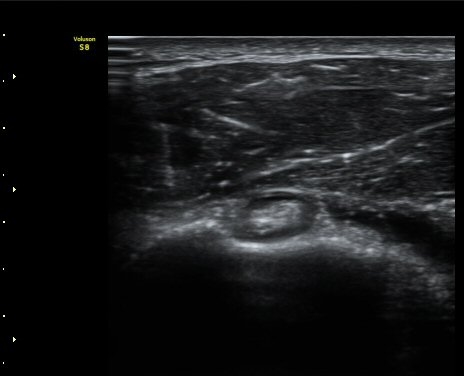

ÀÌµÎ¹Ú±Ù°Ç È¾´Ü¸é°Ë»ç¿¡¼­ °ÇÁÖÀ§¿¡ ¼Ò·®ÀÇ ¼ö¾×Àú·ù¿Í Á¡¾×³¶³» ¾×Àú·ù°¡ °üÂûµÈ´Ù(»çÁø 1, 2).